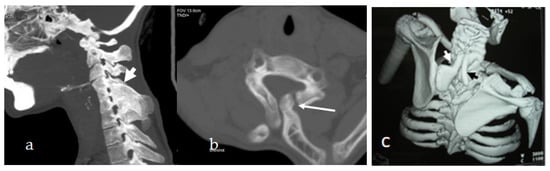

Three-dimensional CT scan showed the round type of os odontoideum which predisposes to myelopathy. 3D reconstruction coronal CT scan of a 14-year-old girl with pseudoachondroplasia showed rounded shape os odontoideum (arrow) and atlanto-axial instability (Figure 4a). Three-dimensional sagittal reconstruction CT showed exaggerated cervical spine lordosis (Figure 4b).

An 18-year-old girl with under-developed secondary sex characteristics, but primary amenorrhoea and cervical vertebral defects can raise our doubts for the diagnosis of MURCS. She showed enormous alterations in the normal sequence of development of Mullerian ducts which resulted in the development of a wide spectrum of reproductive tract abnormalities. Pelvic and genital ultrasound examination revealed vaginal atresia and a rudimentary uterus, which was confirmed by the colposcopy examination showing symmetrical muscular buds instead of a normal uterus, and renal ultrasound showed normal kidneys. The clinical examination revealed a normal growth spurt, but torticollis and cervical kyphosis were the most bothersome complaint. She received abundant sessions of physiotherapy in her first few years of life. The clinical examination showed a short neck with inclination of the head to the same side (fixed torticollis) strongly correlated with cervical kyphosis. She totally lost her spine biomechanics and stiffness was the outcome. Three-dimensional sagittal CT scan showed cervical kyphosis with massive fusion of the cervical vertebrae (extensive fusion of C4–7 associated with fused spinous processes), a deformity that is extremely surprising (Figure 5a). Axial 3D reformatted CT scan of the C7 showed a bony bridge between the omoplate and spine which resulted in the development of an omovertebral bone (Figure 5b).

A-16-year-old girl similarly presented with torticollis since her early life followed by the development of progressive cervico-thoracic kyphosis. Pelvic-renal ultrasound showed a constellation of ovarian aplasia, uterine, vaginal hypoplasia associated with left renal hypoplasia. Thus, the patients have a combination of Mullerian duct aplasia, renal hypolasia, and cervicothoracic somite dysplasia. Three-dimensional reconstruction CT scan in a 16-year-old girl showed torticollis, progressive cervico-thoracic kyphosis, and bilateral omovertebral bones originating from the 7th cervical spine. An apparent omovertebral bone connecting the 7th cervical spine with the superior border of the left scapula (white arrow) gives rise to the development of Springle’s deformity (Figure 5c).

Figure 4. (a,b) Three-dimensional reconstruction coronal CT scan of a 14-year-old girl with pseudoachondroplasia showed rounded shape os odontoideum (arrow) and atlanto-axial instability (a). 3D sagittal reconstruction CT showed exaggerated cervical spine lordosis and atlanto-axial instability (b).

Figure 5. (a,b) Three-dimensional sagittal CT scan of an 18-year-old-girl with MURCS association showed cervical kyphosis with massive fusion of the cervical vertebrae (extensive fusion of C4-7 associated with fused spinous processes), a deformity that is extremely surprising (a). Axial 3D reformatted CT scan of the C7 showed true bony bridge between the omoplate and spine that resulted in the development of omovertebral bone (b). Three-dimensional reconstruction CT scan in a 16-year-old girl presented with torticollis, progressive cervico-thoracic kyphosis and bilateral omo-vertebral bones originated from the 7th cervical spine. Apparent omovertebral bone connecting the 7th cervical spine with the superior border of the left scapula (white arrow) gives rise to the development of Springle’s deformity (c).